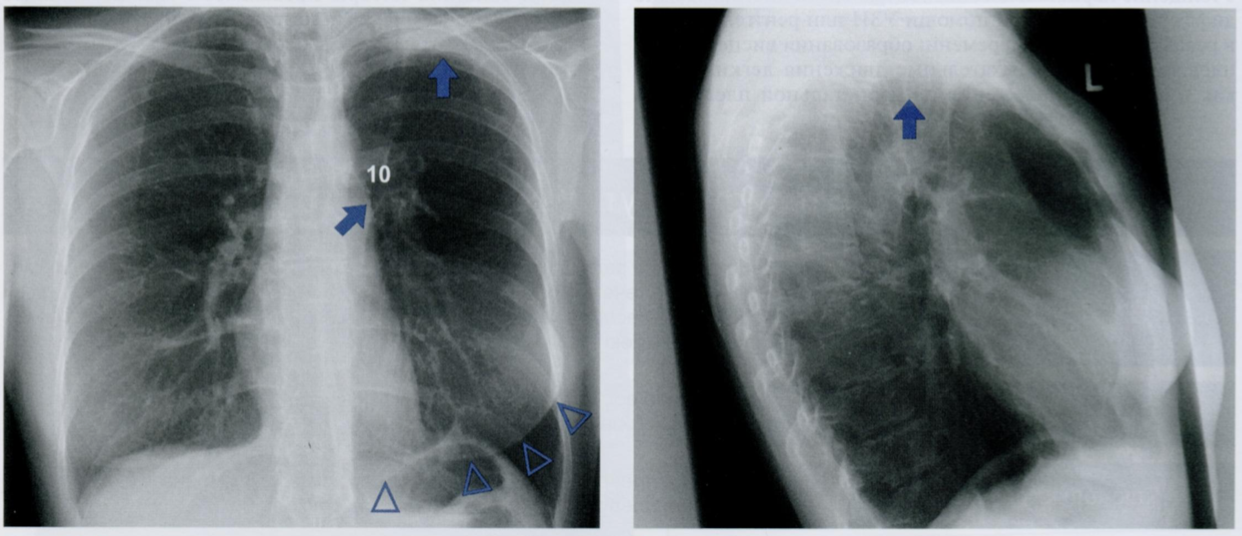

Оцените снимки.

Что из себя представляет фиброз плевры?

Физброз представляет собой грануляционную ткань, которая может вторично обызвествляться.

Верхушечные «шапки» за счет утолщенной плевры часто обнаруживаются в пожилом возрасте, но связывать их с туберкулезным процессом можно лишь при наличии внутрилегочного поражения. В этом случае верхушечные «шапки» более выражены.

На первом снимке показаны двусторонние плевральные «шапки» у пациента с туберкулезом. Натяжение фиброзной ткани на верхушках вызвало смещение обоих корней кверху (косые стрелки).

На рентгенограмме в БП четко видна полосовидная текстура плотного интерстиция (горизонтальные стрелки). Кроме того, на тень сердца проецируются очаги фиброза в переднебазальных участках плевры (косые стрелки, смотрят вниз).